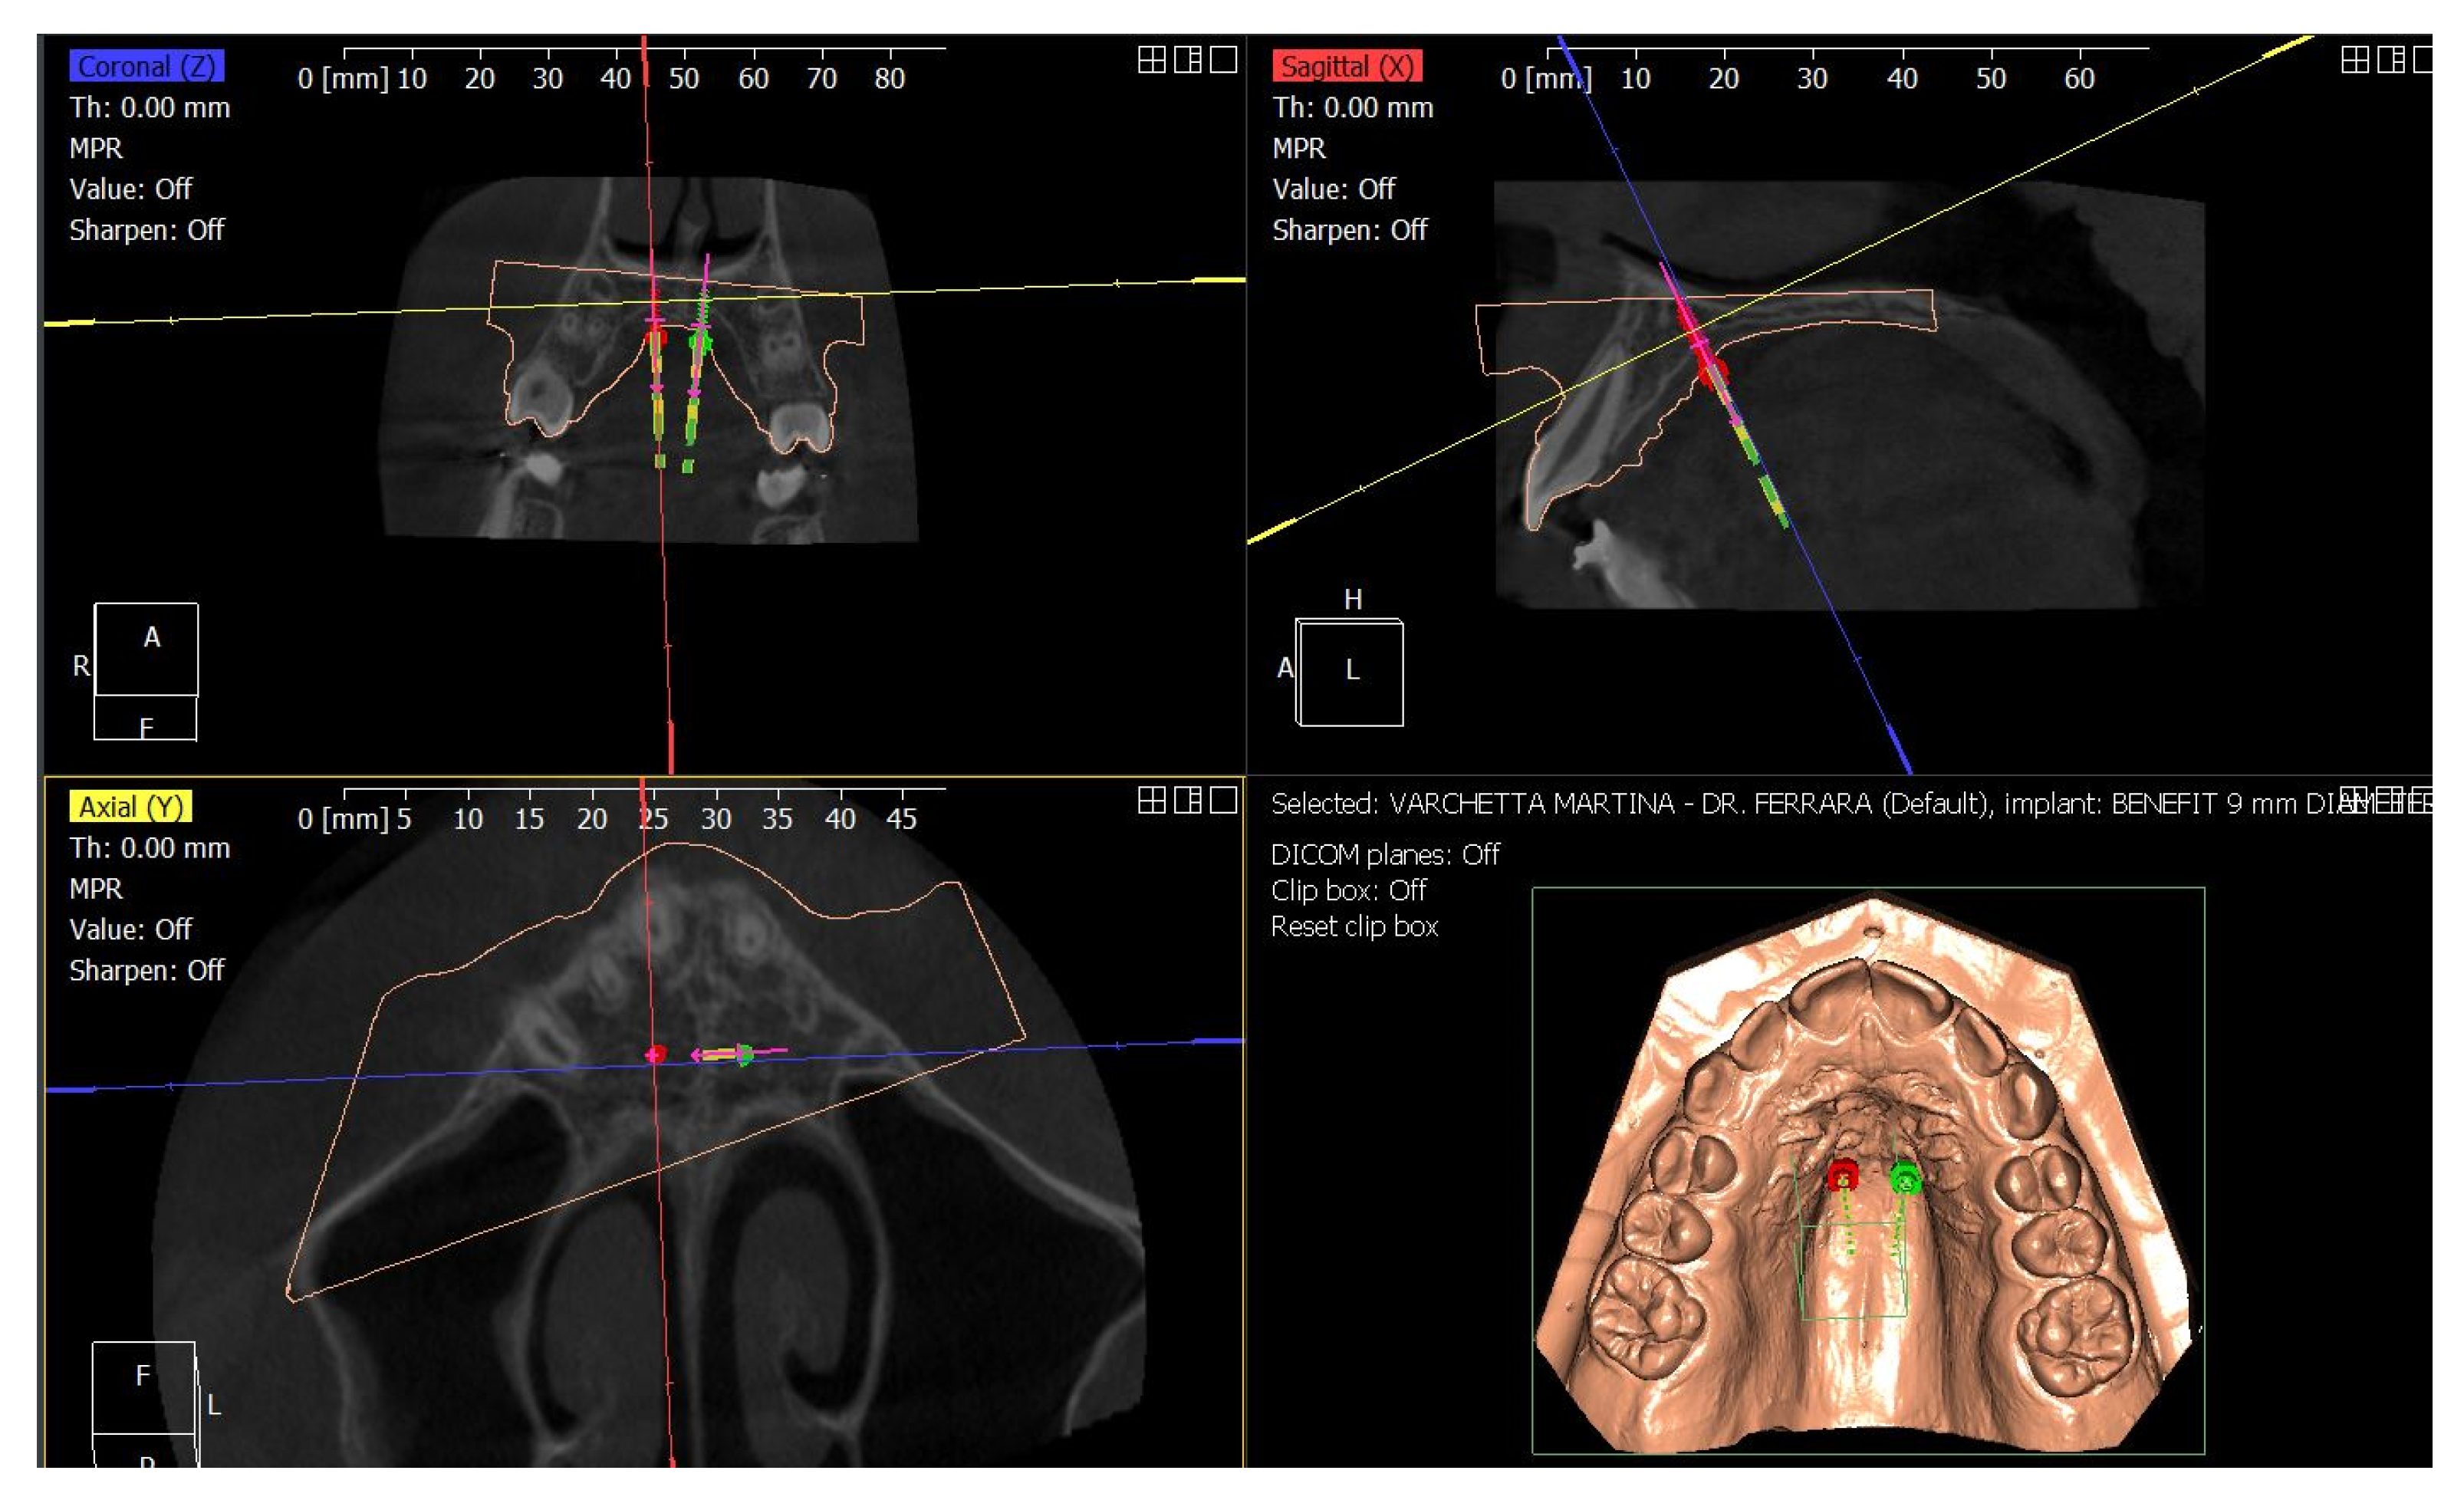

4. Case Report

4.3. Treatment Strategy

4.4. Treatment Progress